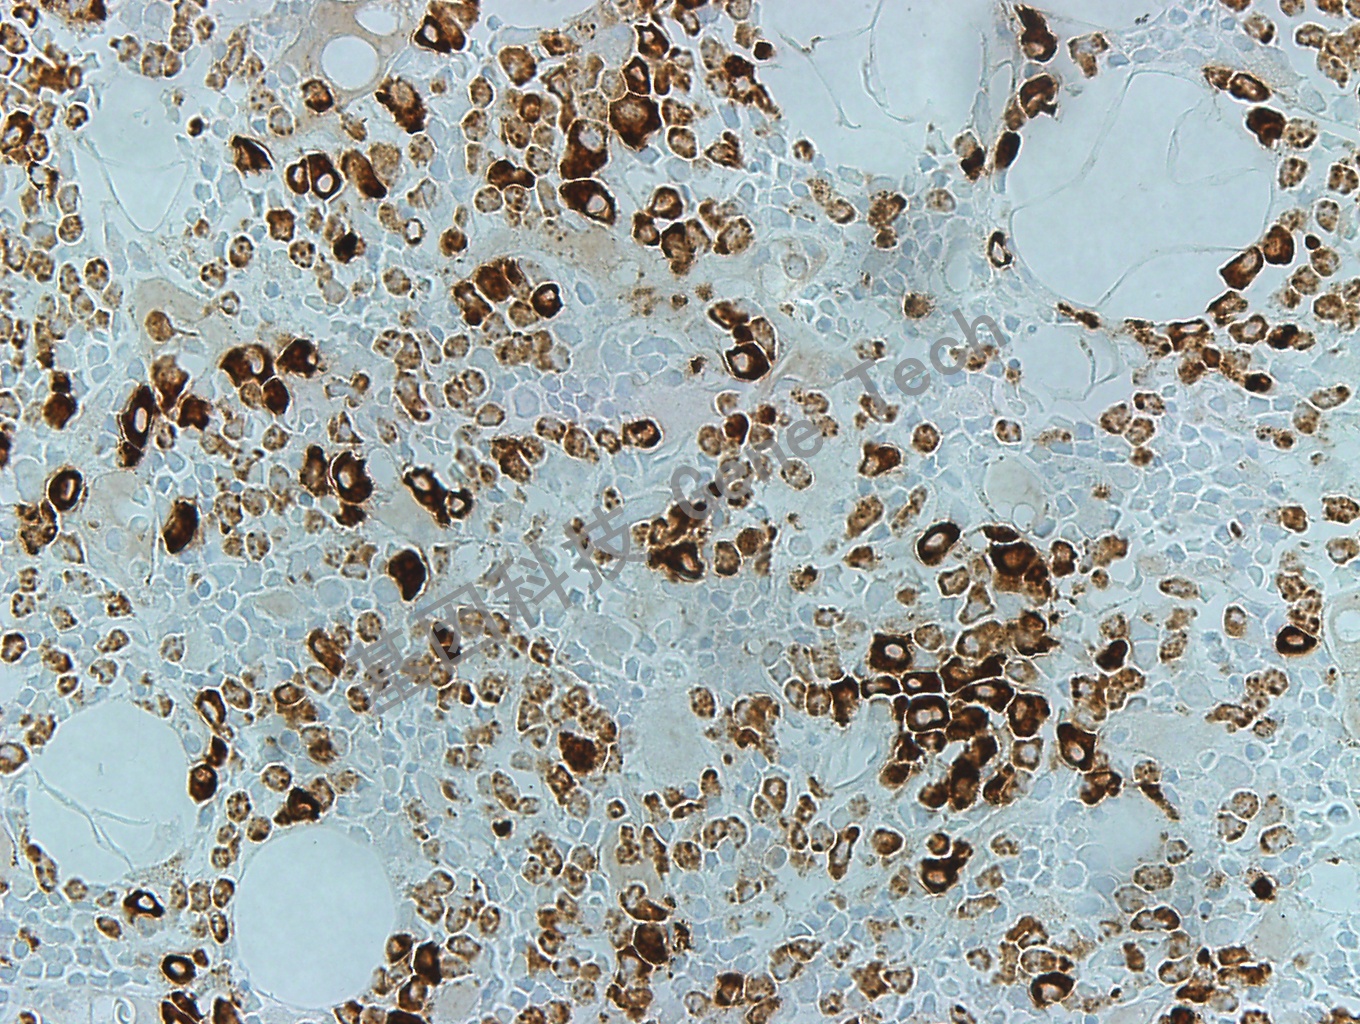

| 簡介:MPO(Myeloperoxidase, 髓過氧化物酶)是粒細(xì)胞在吞噬裂解外來體構(gòu)成中的一個重要酶,對機(jī)體產(chǎn)生和調(diào)節(jié)炎癥反應(yīng)等多方面發(fā)揮作用。主要表達(dá)于中性粒細(xì)胞和單核細(xì)胞,而不表達(dá)于紅細(xì)胞樣前體、淋巴樣細(xì)胞、原核細(xì)胞、肥大細(xì)胞、漿細(xì)胞以及各種上皮源性腫瘤和肉瘤等。是髓系白血病和粒細(xì)胞肉瘤敏感及特異性的標(biāo)記物。主要用于急性白血病免疫分型和粒細(xì)胞肉瘤的診斷,亦可用于急性白血病與一些淋巴瘤的鑒別診斷。 | ||

| 骨髓石蠟切片,用 MPO(GT2032)染色,細(xì)胞漿陽性,DAB 顯色。 | ||